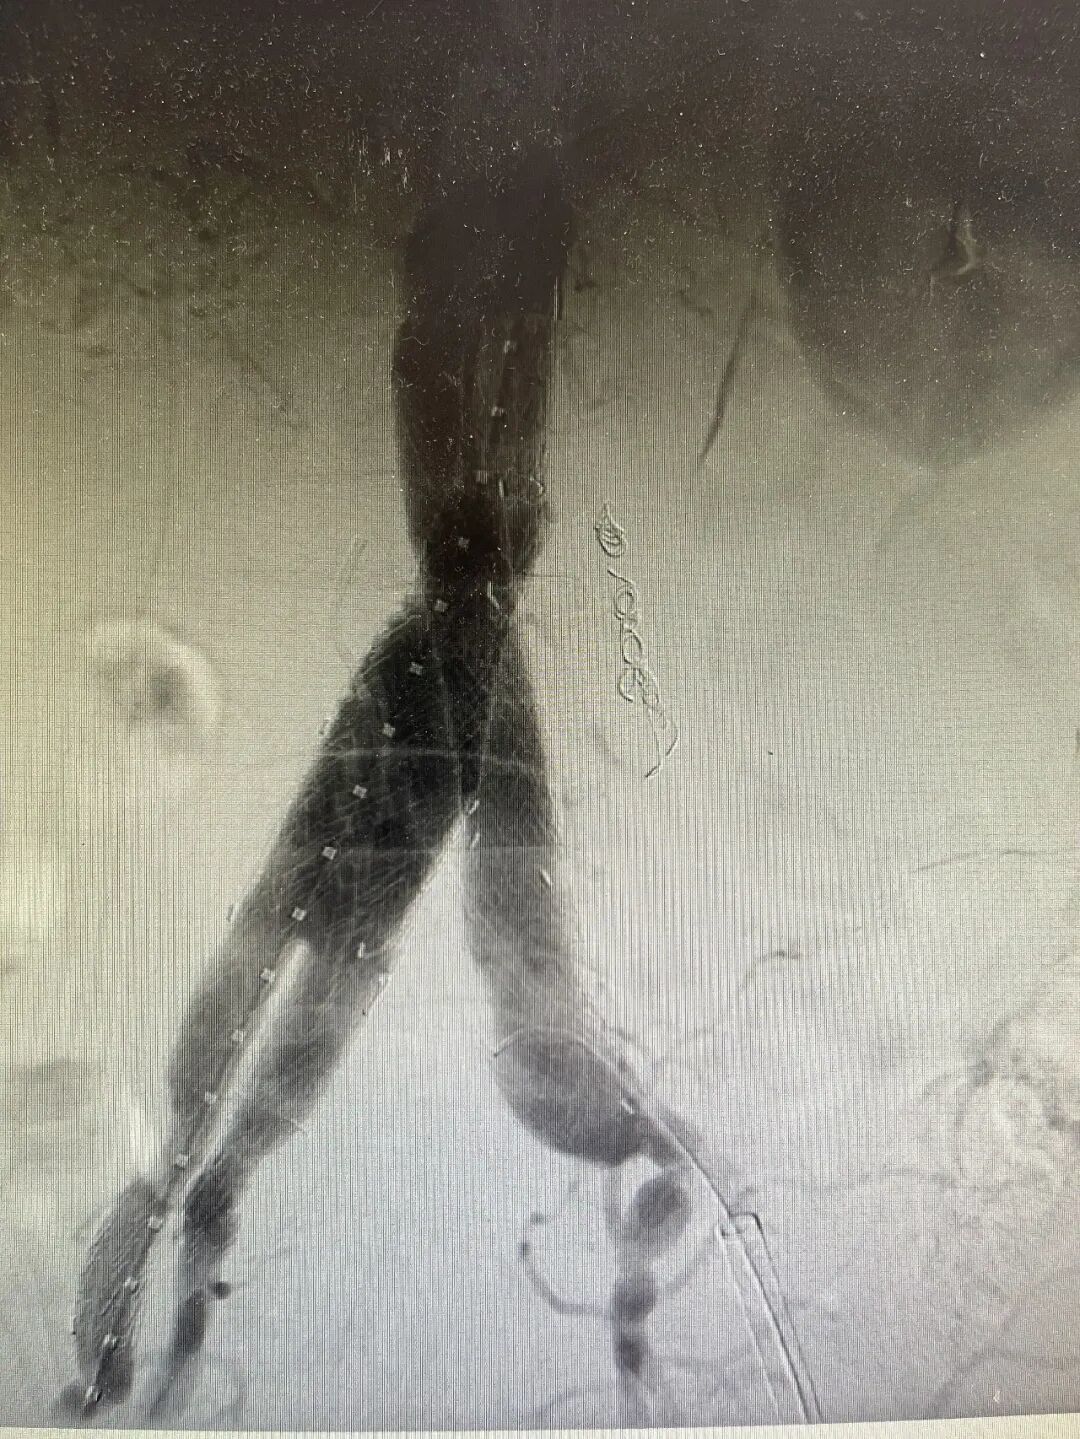

经过术前多学科会诊的详细讨论和周密规划,近日,李清乐教授与皇冠篮球比分网_澳门现金网-球探体育:医院血管外科执行主任孙念峰、主任医师孙春亮周密规划,为这两名患者实施了血管外科微创手术(IBE)。

手术最大的挑战,是如何在隔绝动脉瘤的同时,精准重建髂内动脉。采用腹主动脉分支支架、髂动脉分支支架技术重建腹主动脉、髂总动脉、髂外动脉、髂内动脉,是目前公认的既能隔绝动脉瘤、又能最大限度保留盆腔功能的最优解之一。这项技术操作复杂,对医生的技术和团队的配合要求极高,经过手术团队精细操作,手术顺利结束,患者已顺利出院。